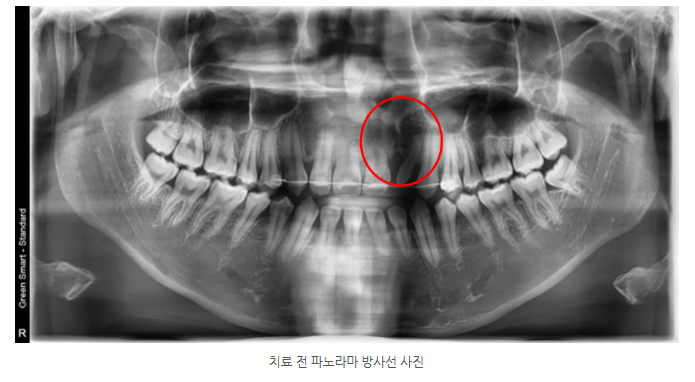

19세 남성

반대교합, 개방교합, 다수의 치간 공간

상악 좌측 측절치 왜소치

구개열 부위 중절치·측절치 치근이 매우 짧은 상태

구개열 부근 치아의 치근이 짧아 전치 이동을 최소화해야 했습니다.